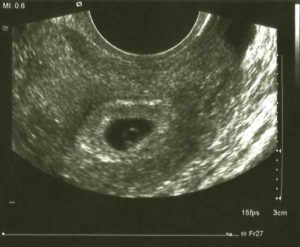

Для установления наличия и срока беременности врач проводит трансвагинальное УЗИ. Этот доступ позволяет лучше рассмотреть полость матки, достовернее измерить размер и оценить структуру плодного яйца.

Помимо визуализации самого плодного яйца врач обязательно оценивает все внутренние органы репродуктивной системы у женщины: матку, шейку, яичники, а также мочевой пузырь.

У худых женщин на ранних неделях плодное яйцо иногда бывает видно и с помощью трансабдоминального доступа.

На раннем сроке с 4 по 6 недели срок беременности устанавливают по диаметру плодного яйца. Для этого врач проводит измерение диаметра плодного яйца по его внутреннему контуру в 3 взаимоперпендикулярных плоскостях.

Трансвагинальное УЗИ покажет плодное яйцо в полости матки, когда наступят 4,5 – 5,0 недель беременности. Стоит отметить, что врачи считают продолжительность беременности с первого дня крайних месячных.

Плодным яйцом называются зародышевые оболочки и зародыш. Снаружи оно окружено хорионом – ворсистым слоем, который обеспечивает прикрепление к стенке матки и налаживает питание эмбриона от организма матери.

Будущий ребенок на УЗИ выглядит как округлое образование, к пятой неделе его размер составляет несколько миллиметров. После зачатия в матке яйцеклетка закрепляется на 6-10 день с момента оплодотворения и начинает стремительно расти.